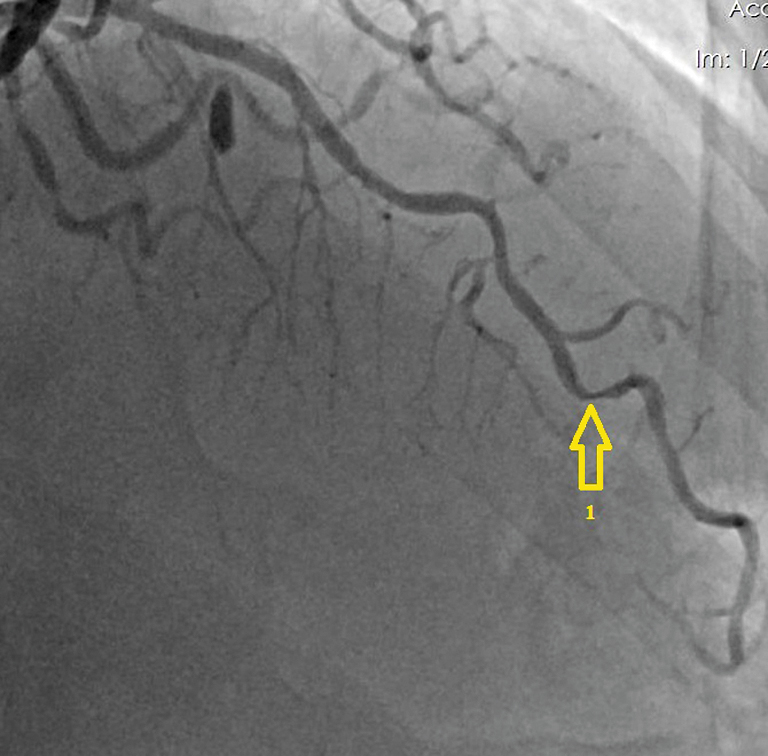

В 2020 г. пациент обратился к кардиологу с жалобами на боли в области сердца при физической нагрузке. По данным скринингового цветного дуплексного сканирования брахиоцефальных артерий и дальнейшей их ангиографии визуализирован 80% рестеноз ВСА слева (рис. 2), 97% стеноз (субокклюзия) ВСА справа (рис. 3). По результатам коронарографии диагностирован 90% стеноз ПНА (рис. 4).

Рис. 4. Коронарография: 1 — 90% стеноз передней нисходящей артерии. / Fig. 4. Coronary angiography: 1 — 90% stenosis of the left anterior descending artery.